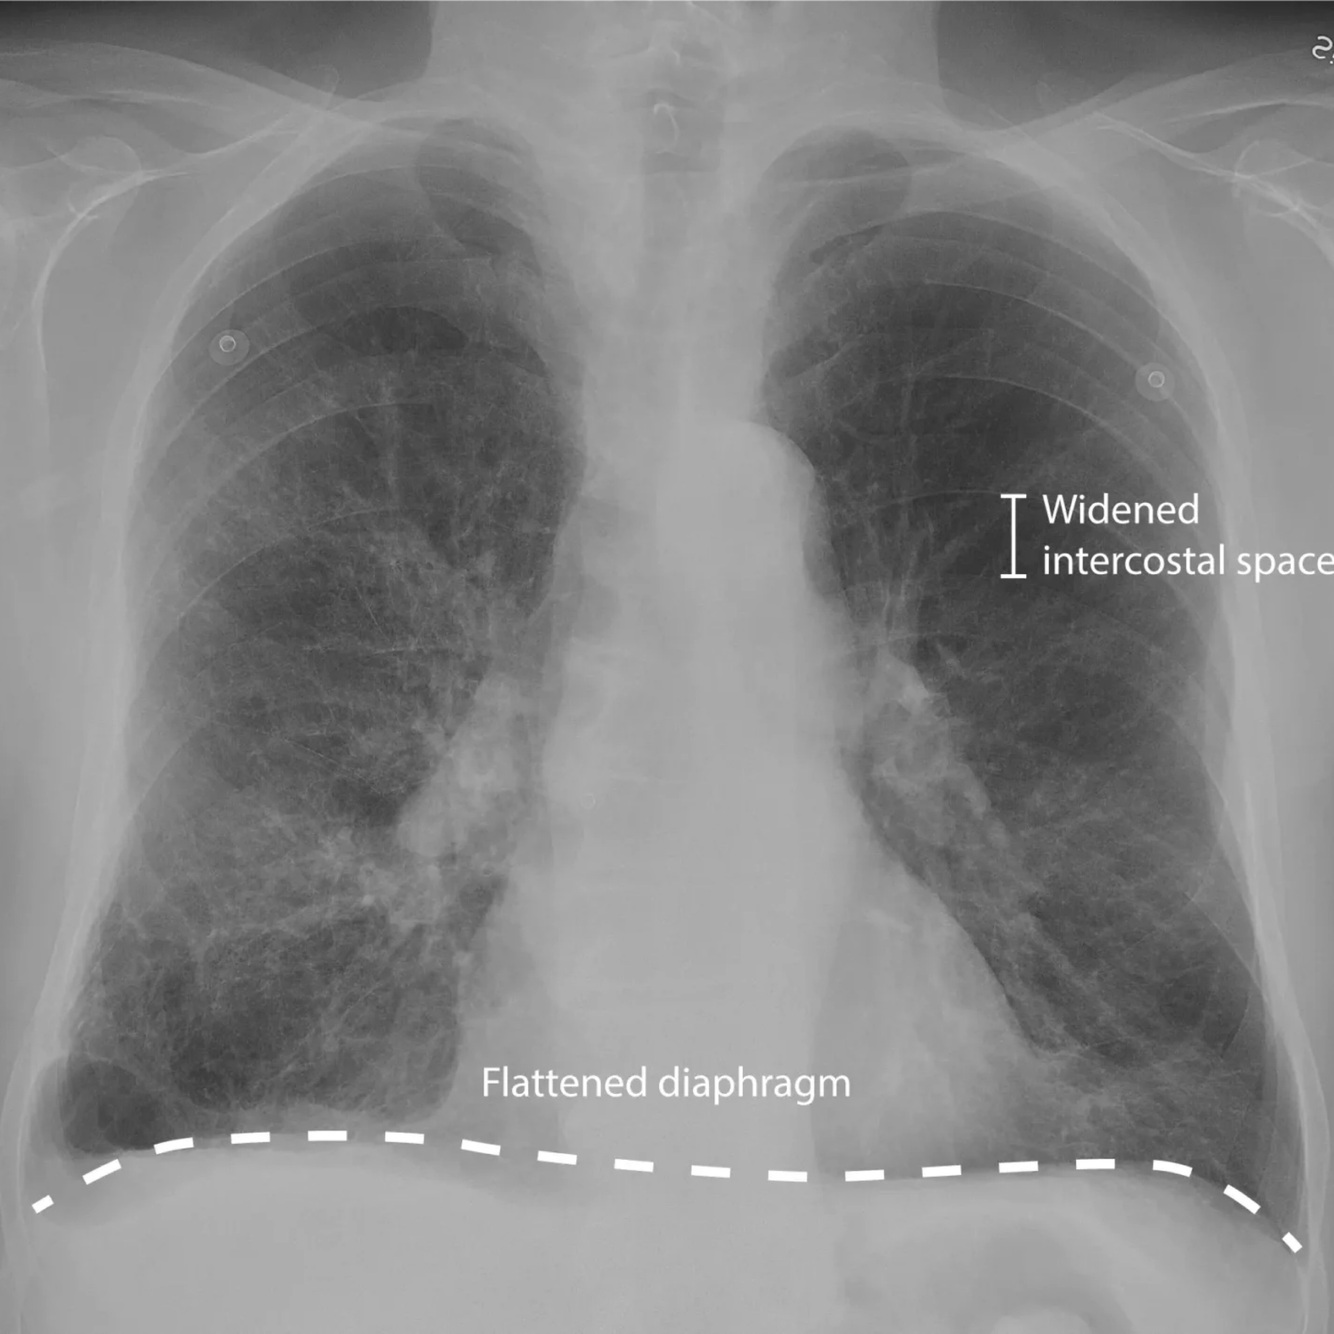

¿Cómo encontraremos una Rx de Tórax en px con EPOC?

A

-Volumen pulmonar aumentado

-Diafragmas planos y abatidos

-Silueta cardiaca alargada

-Aumento de espacio retroesternal

-Márgenes broncovasculares visibles

¿Cómo veremos una Rx en un enfisema predominante?

-Hiperclaridad difusa

-Disminución de las marcas vasculares

-Aumento de diámetros del tórax

-Aplanamiento del diafragma

-Ampliación y horizontalización de arcos costales